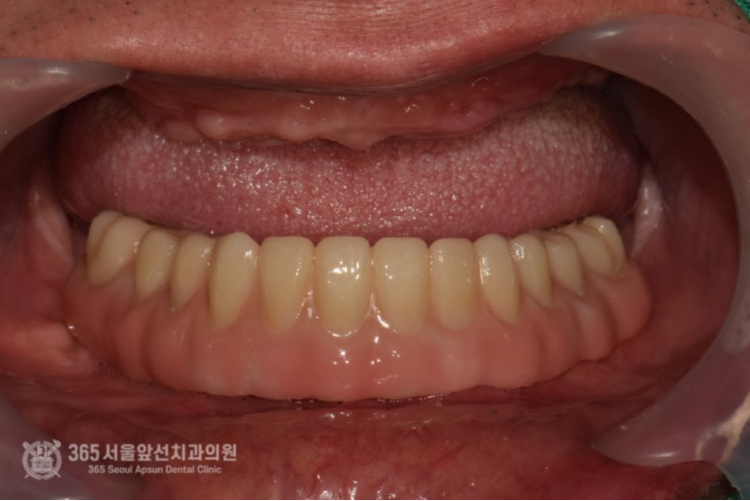

위 사진은 All on X라는 보철물 내부에 들어가는 금속구조물입니다. 정확한 용어로는 Mesostructure라고 합니다. (다른 환자분 케이스에서 사용된 금속구조물이지만 이해를 돕기위해 참고용으로 넣었습니다) All on X 보철물의 특징상, 단단한 강도가 매우 중요하며 보철물의 적합성이 매우 중요합니다. 따라서 정교한 작업이 필요하며 다소 번거롭더라도 여러번의 작업이 필요합니다. 촬영일시 : 2025.01.02. 아래쪽 보철물은 All on X 라고 하여 메탈 바가 들어가는 복잡한 방식의 보철물이기에 정확도가 생명입니다. 따라서 번거롭더라도 석고 모형 상에서 한번 맞춰보는 작업도 필요하기에 진행하였습니다. 위턱에 식립한 임플란트가 단단하게 굳었을때 쯤 임플란트에 치유지대주라는 단추를 연결합니다. 이제 슬슬 본을 떠도 되겠습니다. 양측 어금니 부위에 뼈가 매우 부족하여 상악동 거상술을 진행하였던 부위도 뼈가 생성되는게 관찰됩니다. 아래턱 보철물이 입안에 위치된 상태입니다. 아래만 맞춰봤는데 환자분은 벌써부터 기대감이 대단하십니다. 이 단계쯤되면 저도 두근두근합니다ㅎㅎ 위아래 보철물이 모두 장착된 상태에서의 파노라마 엑스레이 사진입니다. 제가 치료해드렸지만 제가 봐도 만족스럽습니다 ㅎㅎ 촬영일시 : 2025.01.15. 촬영일시 : 2025.01.15. 위아래 보철물이 모두 들어간 상태의 구강내 사진입니다. 환자분은 치료가 끝나고 눈물을 글썽글썽하셨습니다. 전체 임플란트 치료는 그만큼 요구되는 수준이 높고 의사도 힘들고 환자분들께서도 힘들지만 치료가 마무리 되고 나면 기억에 많이 남는것같습니다. 오늘도 매우 뼈가 좋지 않았던 환자분의 고난이도 치료 증례를 소개해드렸습니다. 앞으로도 좋은 치료 증례로 도움이 될 수 있게 노력하겠습니다. 지금까지 365일 열린 가까운 서울대학교 치과병원을 지향하는 주안동치과 365서울앞선치과였습니다. 감사합니다. [ 치료기간: 2024년 7월3일 ~ 2025년 1월 15일 ] ※ 365서울앞선치과의원의 모든 포스팅은 각 진료과 의료진이 직접 작성합니다. 365서울앞선치과의원 블로그의 임상 케이스 게시물은 환자분께 의학적으로 정확하고 상세한 정보를 드리기 위해 각 진료과 의료진이 직접 작성하며, 모든 증례 사진은 본원 의료진이 직접 시술한 증례를 촬영한 것으로, 의료법 제23조, 제56조에 의거하며 환자분의 동의를 얻어 포스팅에 사용하였습니다. 또한 해당 케이스는 본 환자분의 치료 결과이며, 환자 상태에 따라 치료의 결과는 달라질 수 있습니다. |